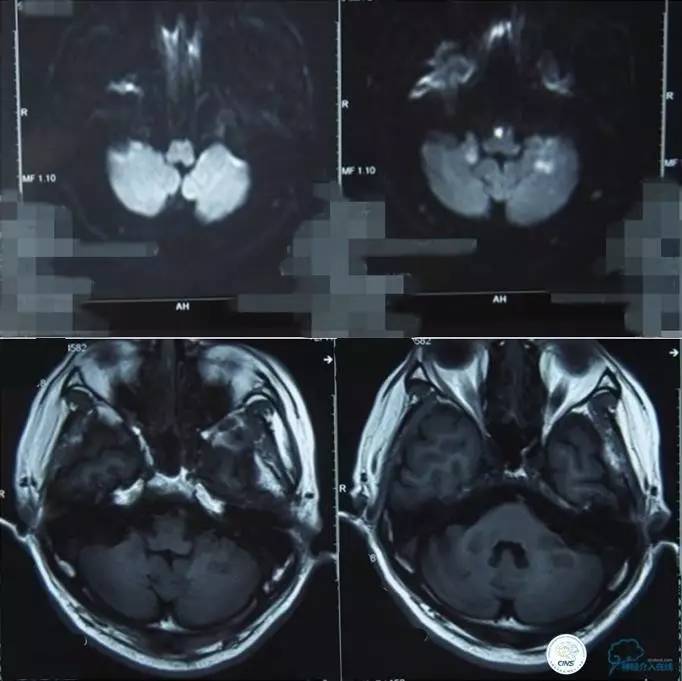

▼影像学资料

入院后,患者症状稍有加重,出现走路不稳,查体发现两手指鼻不稳。行颅脑MRI检查。给予双抗血小板、调脂、改善脑循环、营养神经等药物治疗。立普妥20mg qn。实验室检查:LDL-C:3.31mmol/L。

▼颅脑CT灌注扫描

▼2014-12-08

▼Apollo 3.0*13mm